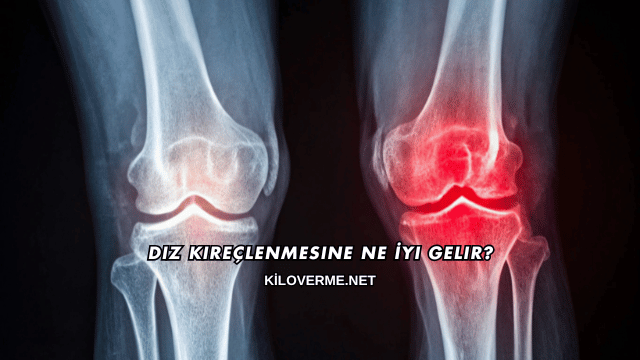

Diz kireçlenmesi, özellikle orta yaş ve üzerindeki kişilerde sık görülen, eklem kıkırdağının aşınmasıyla ortaya çıkan bir rahatsızlıktır. Bu durum hareket kabiliyetini azaltarak günlük yaşamı olumsuz etkileyebilir. Diz kireçlenmesine ne iyi gelir sorusu, ağrılarını hafifletmek ve yaşam kalitesini artırmak isteyen pek çok kişi tarafından araştırılmaktadır.